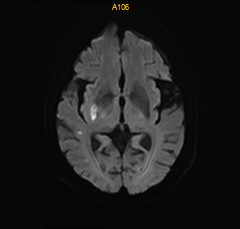

术后DWI:磁共振见少许新鲜脑梗死。

什么叫桡鞘【例久弥新】寻道于桡——瑞康通5.5F IntroSky X导管鞘经桡动脉行右侧大脑中动脉取栓一例_https://www.jmylbn.com_新闻资讯_第28张